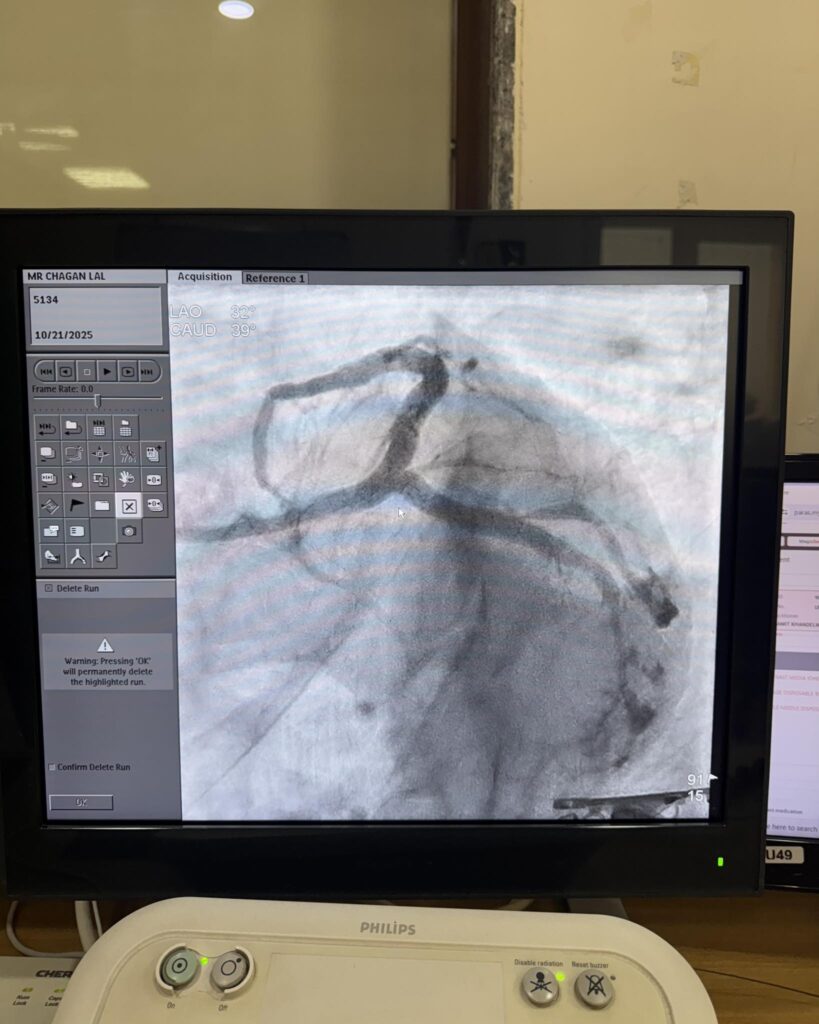

Take a look at our clinic, equipment, and the team dedicated to your cardiac care.

Visit our clinic and experience world-class cardiac care.